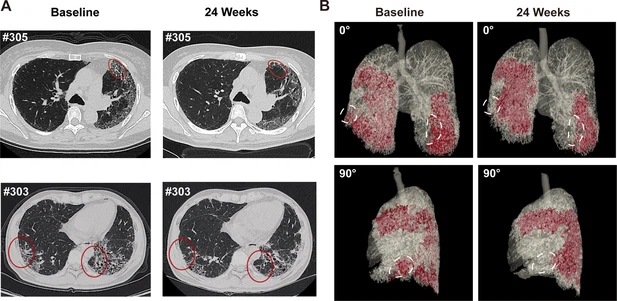

- 蜂窩狀病變消退:1M劑量組中兩名患者(#303、#305)的HRCT顯示下葉蜂窩狀病變減少(圖4A),三維重建證實下葉病變區域縮小(圖4B)。

(A) 患者#305和#303在基線和REGEND001治療后24周的代表性肺部CT圖像。紅色圓圈表示蜂窩狀病變消退。(B) 患者#305連續CT圖像的三維可視化。紅色區域表示細胞治療前后肺部受損區域(網狀和蜂窩狀)。白色圓圈表示下葉病變消退。

總結:REGEND001高劑量治療可顯著改善IPF患者運動能力及生活質量,并在部分患者中實現肺纖維化結構的可逆性修復(尤其下葉)。療效呈現劑量依賴性,且與細胞分布機制相關。盡管樣本量有限,但結果為再生療法逆轉肺纖維化提供了首個影像學證據,需擴大隊列驗證長期效果及機制。